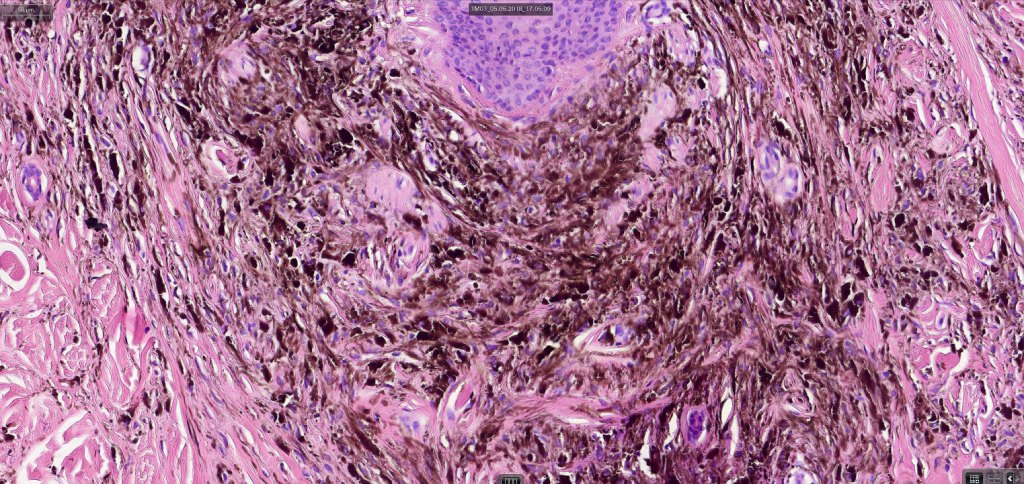

Common blue nevus

Common blue nevus shows a predilection for the backs of the hands & feet, buttocks, face & scalp althought any site can be affected. It presents as a sharply delineated approximately 1.0 cm diameter slate blue or blue/black papulo/nodule. Congenital, eruptive, targetoid, plaque & desmoplatic/hypopigmented variants are recognised. Common blue nevi have also been described in the cervix, oral mucosa, conjunctiva & sclera, breast etc.

Exceptionally, melanoma is a complication

Histologically, it is characterized by a dense population of spindled, dendritic melnanocytes & melanophages with variable fibrosis. It may sometimes represent a component of a combined nevus. Mitotic activity is not usually present and pleomorphism is absent (see atypical blue nevus below). Involvement of the arrector pili muscle is not uncommon.

Very exceptionally, blue nevus also involves the epidermis (compound blue nevus).